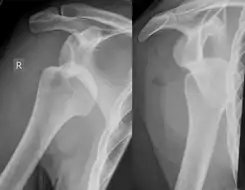

Luxación de hombro derecho con lesión de Hill Sachs

La mayor parte de estas fracturas se encuentran a través de estudios radiológicos convencionales. Una radiografía posteroanterior con el brazo en rotación interna ofrece una buena visión del defecto, mientras que visiones axilares con el brazo en rotación externa tienden a ocultarlo. La sensibilidad y especificidad de la radiografía se encuentra en un 65 % y 67 %, respectivamente. La ultrasonografía también ha demostrado ser un método útil para identificar esta lesión, con una sensibilidad del 96 % y una especificidad del 100 %.